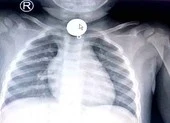

Ông Đ. nhập viện ngày 1-4 với chẩn đoán viêm phổi, tràn dịch màng phổi trái, bệnh phổi tắc nghẽn mạn tính. Sau đó, bệnh nhân được nội soi phế quản ống mềm và nghi ngờ có dị vật ở phế quản thùy dưới trái.

Ngày 21-4, bệnh nhân đã được nội soi phế quản ống mềm, lấy được dị vật là mảnh xương hình khối, kích thước khoảng 12 x 13 x 11 mm.

Bác sĩ tại bệnh viện này cho biết quá trình lấy dị vật hơi khó khăn do dị vật nằm đã lâu trong lòng phế quản. Dị vật phế quản có thể gây những biến chứng cấp tính như ngưng thở, hay có thể gây nhiễm trùng phế quản phổi đe dọa nghiêm trọng đến tính mạng bệnh nhân.